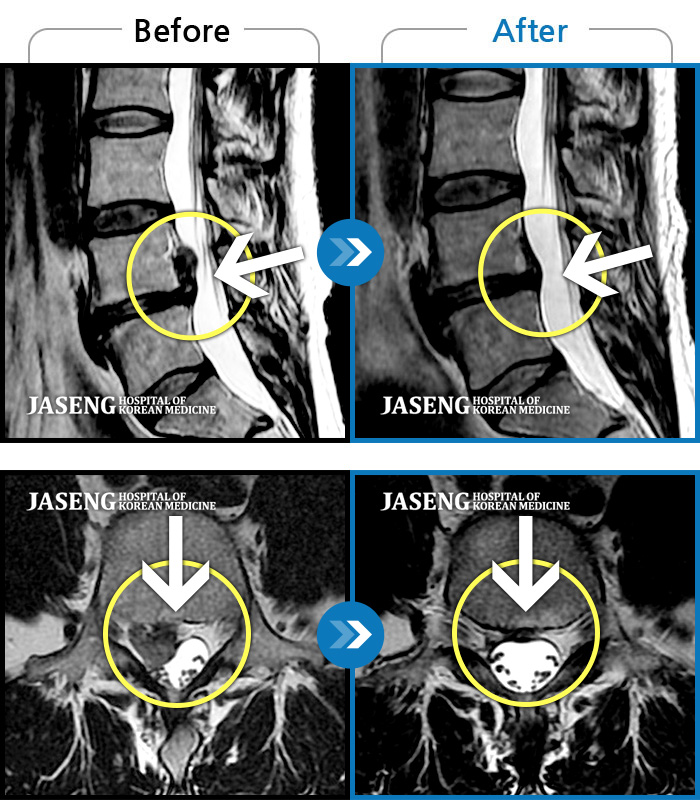

MRI 치료사례

허리디스크

허리굽히는 동작을 한 후 우측 골반통증 및 우측 하지외측 저림, 근력저하가 있었다.

촬영시기

2023.06.15 ~ 2024.03.29

허리숙이는 일을 한 후 급격하게 발생한 우측하지 방사통, 보행장애, 야간통이 있었다.

2023.07.29 ~ 2023.12.09